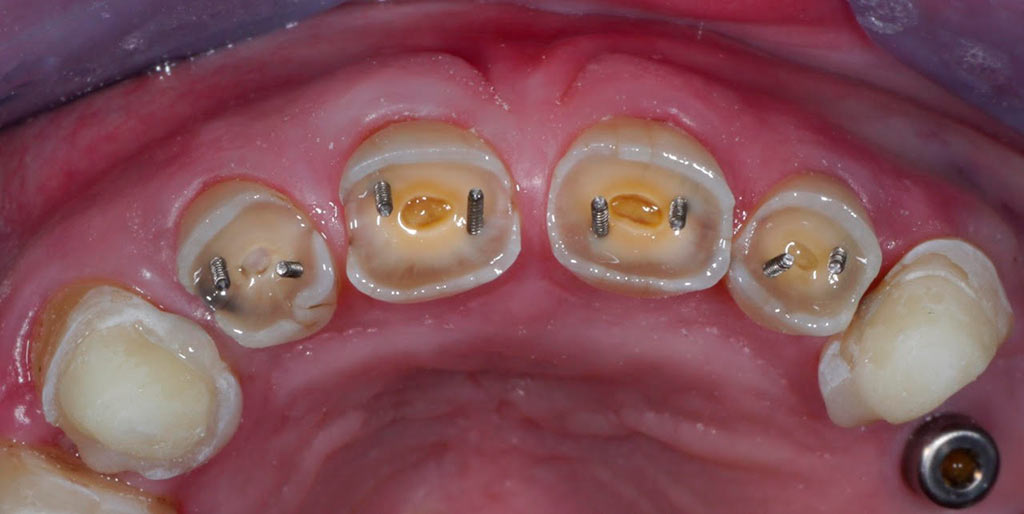

Completa inmediata,cirugía guiada, prótesis, puente de zirconio

Rehabilitacion de paciente con destrucción dental